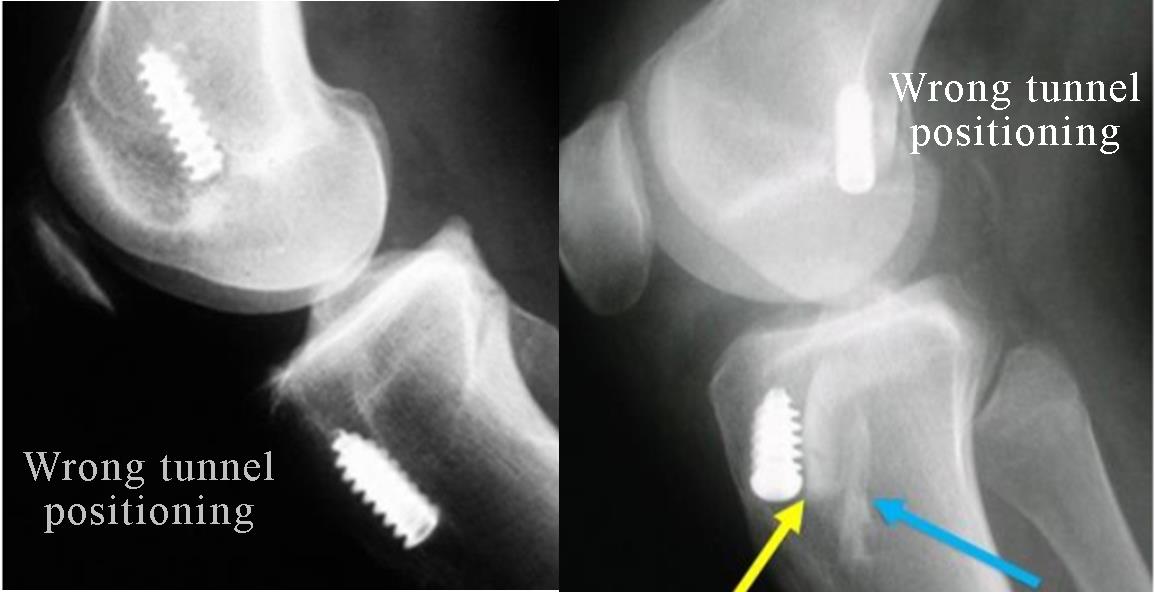

The failed ACL and other ligament reconstruction have many causes but in majority of the cases there will be technical error in the non-anatomic graft positioning. Some of the other common causes include:

The knee is first evaluated and any scar tissue is removed. If the hardware placed earlier is blocking the way of the ideal tunnel placement, then it is removed.

Then doctor makes the tunnels in the right position and then passes the graft through the tunnel and fixes it with metal or bio absorbable implants.